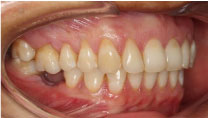

The functional findings revealed a 2 mm. extrusion of tooth 1.6 and gingival recession due to the early loss of tooth 4.6 (Figure 1).

Figure 1: Extrusion of piece 1.6. View Figure 1

Chief complaint: Complete mouth restauration. The initial clinical examination indicated the presence of several restorations, tooth 4.6 missing for four years and extrusion of tooth 1.6, invading the occlusal space.

The functional findings revealed a 2 mm. extrusion of tooth 1.6 and gingival recession due to the early loss of tooth 4.6. A conservative treatment was planned involving Orthodontics, Oral Rehabilitation and Implantology.